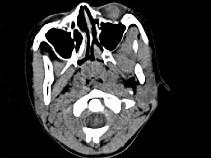

女,8岁,头痛,鼻塞半年余,CT如图所示,最可能诊断为 ( )A、神经纤维瘤B、咽后脓肿C、鼻咽部炎症D、腺样体肥大E、鼻咽癌

问题 女,8岁,头痛,鼻塞半年余,CT如图所示,最可能诊断为 ( )

选项 A、神经纤维瘤 B、咽后脓肿 C、鼻咽部炎症 D、腺样体肥大 E、鼻咽癌

答案 D